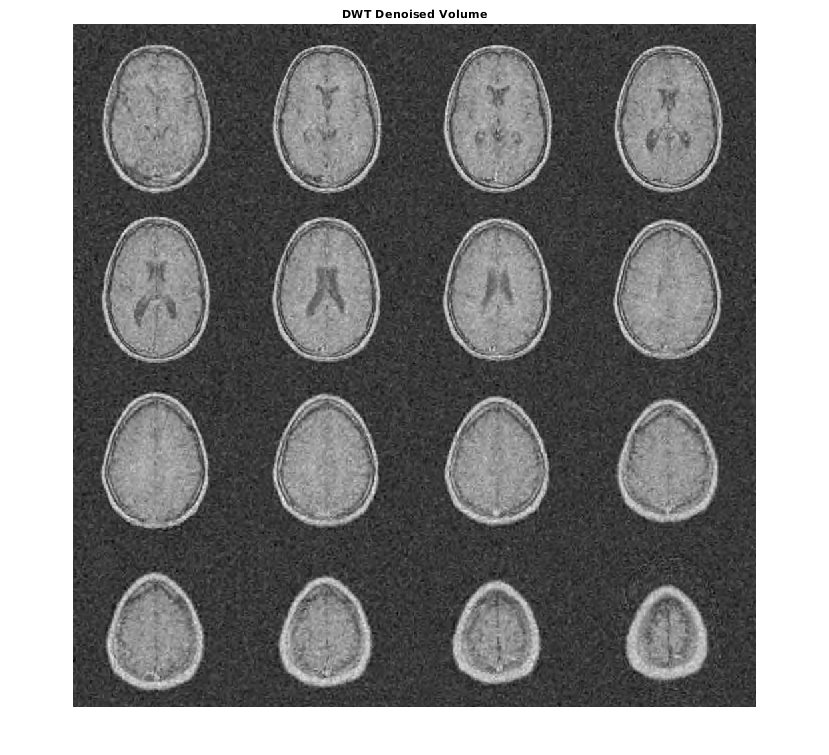

sphrDEC = wavedec3(sphr,2,'sym4','mode','per'); sphrDEC.dec{1} = zeros(size(sphrDEC.dec{1})); for kk = 2:8 sphrDEC.dec{kk} = zeros(size(sphrDEC.dec{kk})); end sphrrecDWT = waverec3(sphrDEC); figure; montage(reshape(sphrrecDWT,[64 64 1 64]),'DisplayRange',[]) title('DWT Level 2 Details');

Увеличьте масштаб изображений и в DT-CWT и в монтаже DWT, и вы будете видеть, как видный блокирующиеся артефакты в деталях DWT сравниваются с DT-CWT.

[imrecDTCWT,imrecDWT] = helperCompare3DDenoising(origMRI,noisyMRI); figure; montage(reshape(imrecDTCWT,[128 128 1 16]),'DisplayRange',[]); title('DT-CWT Denoised Volume'); figure; montage(reshape(imrecDWT,[128 128 1 16]),'DisplayRange',[]); title('DWT Denoised Volume');